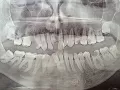

Добрый день! Депульпировали 6-ку внизу. Со стороны щеки стенка зуба почти сравнялась с десной, а другая стенка - в норме. Можно ли нарастить этот жевательный зуб или лучше сделать на него вкладку с коронкой? Заранее, благодарю за совет.

Однозначно, необходимо восстанавливать зуб при помощи культевой вкладки и коронки.

Даже не думайте, восстановление композитом чревато отломом стенки, что в последствии приведет к удалению зуба.